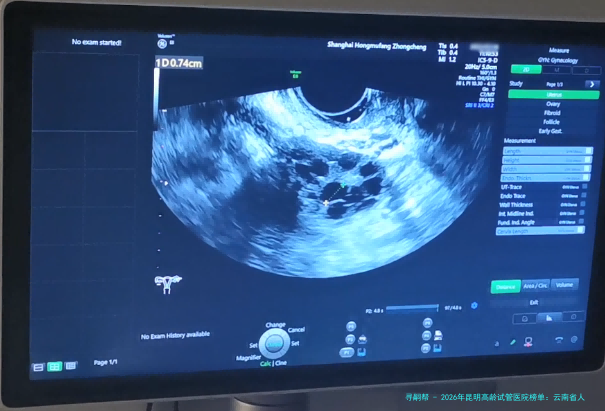

以上便是“2026年昆明高龄试管婴儿医院榜单:云南省人民医院、昆明市妇幼保健院等力量机构详细解释附试管婴儿费用与医生选择指南”,这些医每人平均来自标准医院,具有丰富临床经验和精湛技术,口碑经得起商场测验。想察看医生图片例子、线上当面诊断、认知医生,咨询本站客服,获取一对一专用客服交流服务!